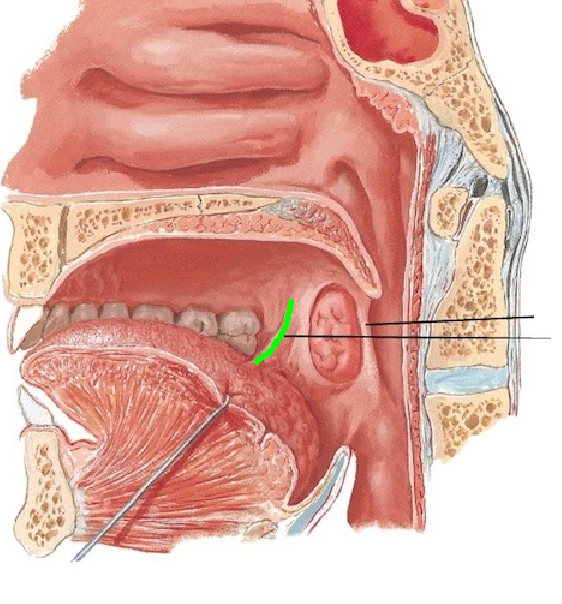

Palatoglossal arch

Palatine tonsils

Opening to parotid duct

Entrance to auditory tube